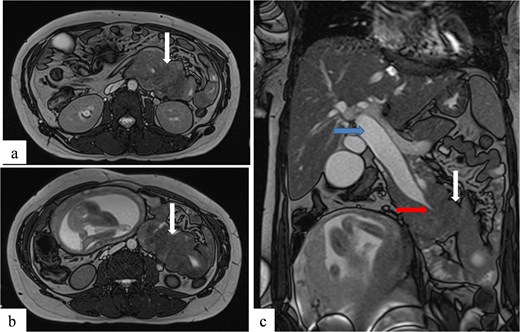

To better assess the biliary anatomy and clarify the cause of obstruction, a MR cholangiopancreatography (MRCP) was performed 2 days later. It confirmed the duodenojejunal invagination and demonstrated the involvement of the terminal bile duct within the intussuscepted segment (Fig. 4). An ectopic biliopancreatic confluence was also identified, draining into the fourth portion of the duodenum, likely predisposing the bile duct to traction and resulting in upstream dilation (Fig. 5).

Axial (a, b) and coronal (c) T2-weighted TrueFISP MR images confirming the duodenojejunal intussusception (white arrows) and showing inclusion of the terminal bile duct within the intussuscepted segment (red arrow), resulting in significant upstream biliary dilatation (blue arrow).

Coronal MR cholangiopancreatographic image showing an ectopic biliopancreatic confluence draining into the fourth portion of the duodenum (arrow at the bottom), which likely predisposed the biliary system to traction during the intussusception, resulting in upstream biliary duct dilatation (two arrows at the top).